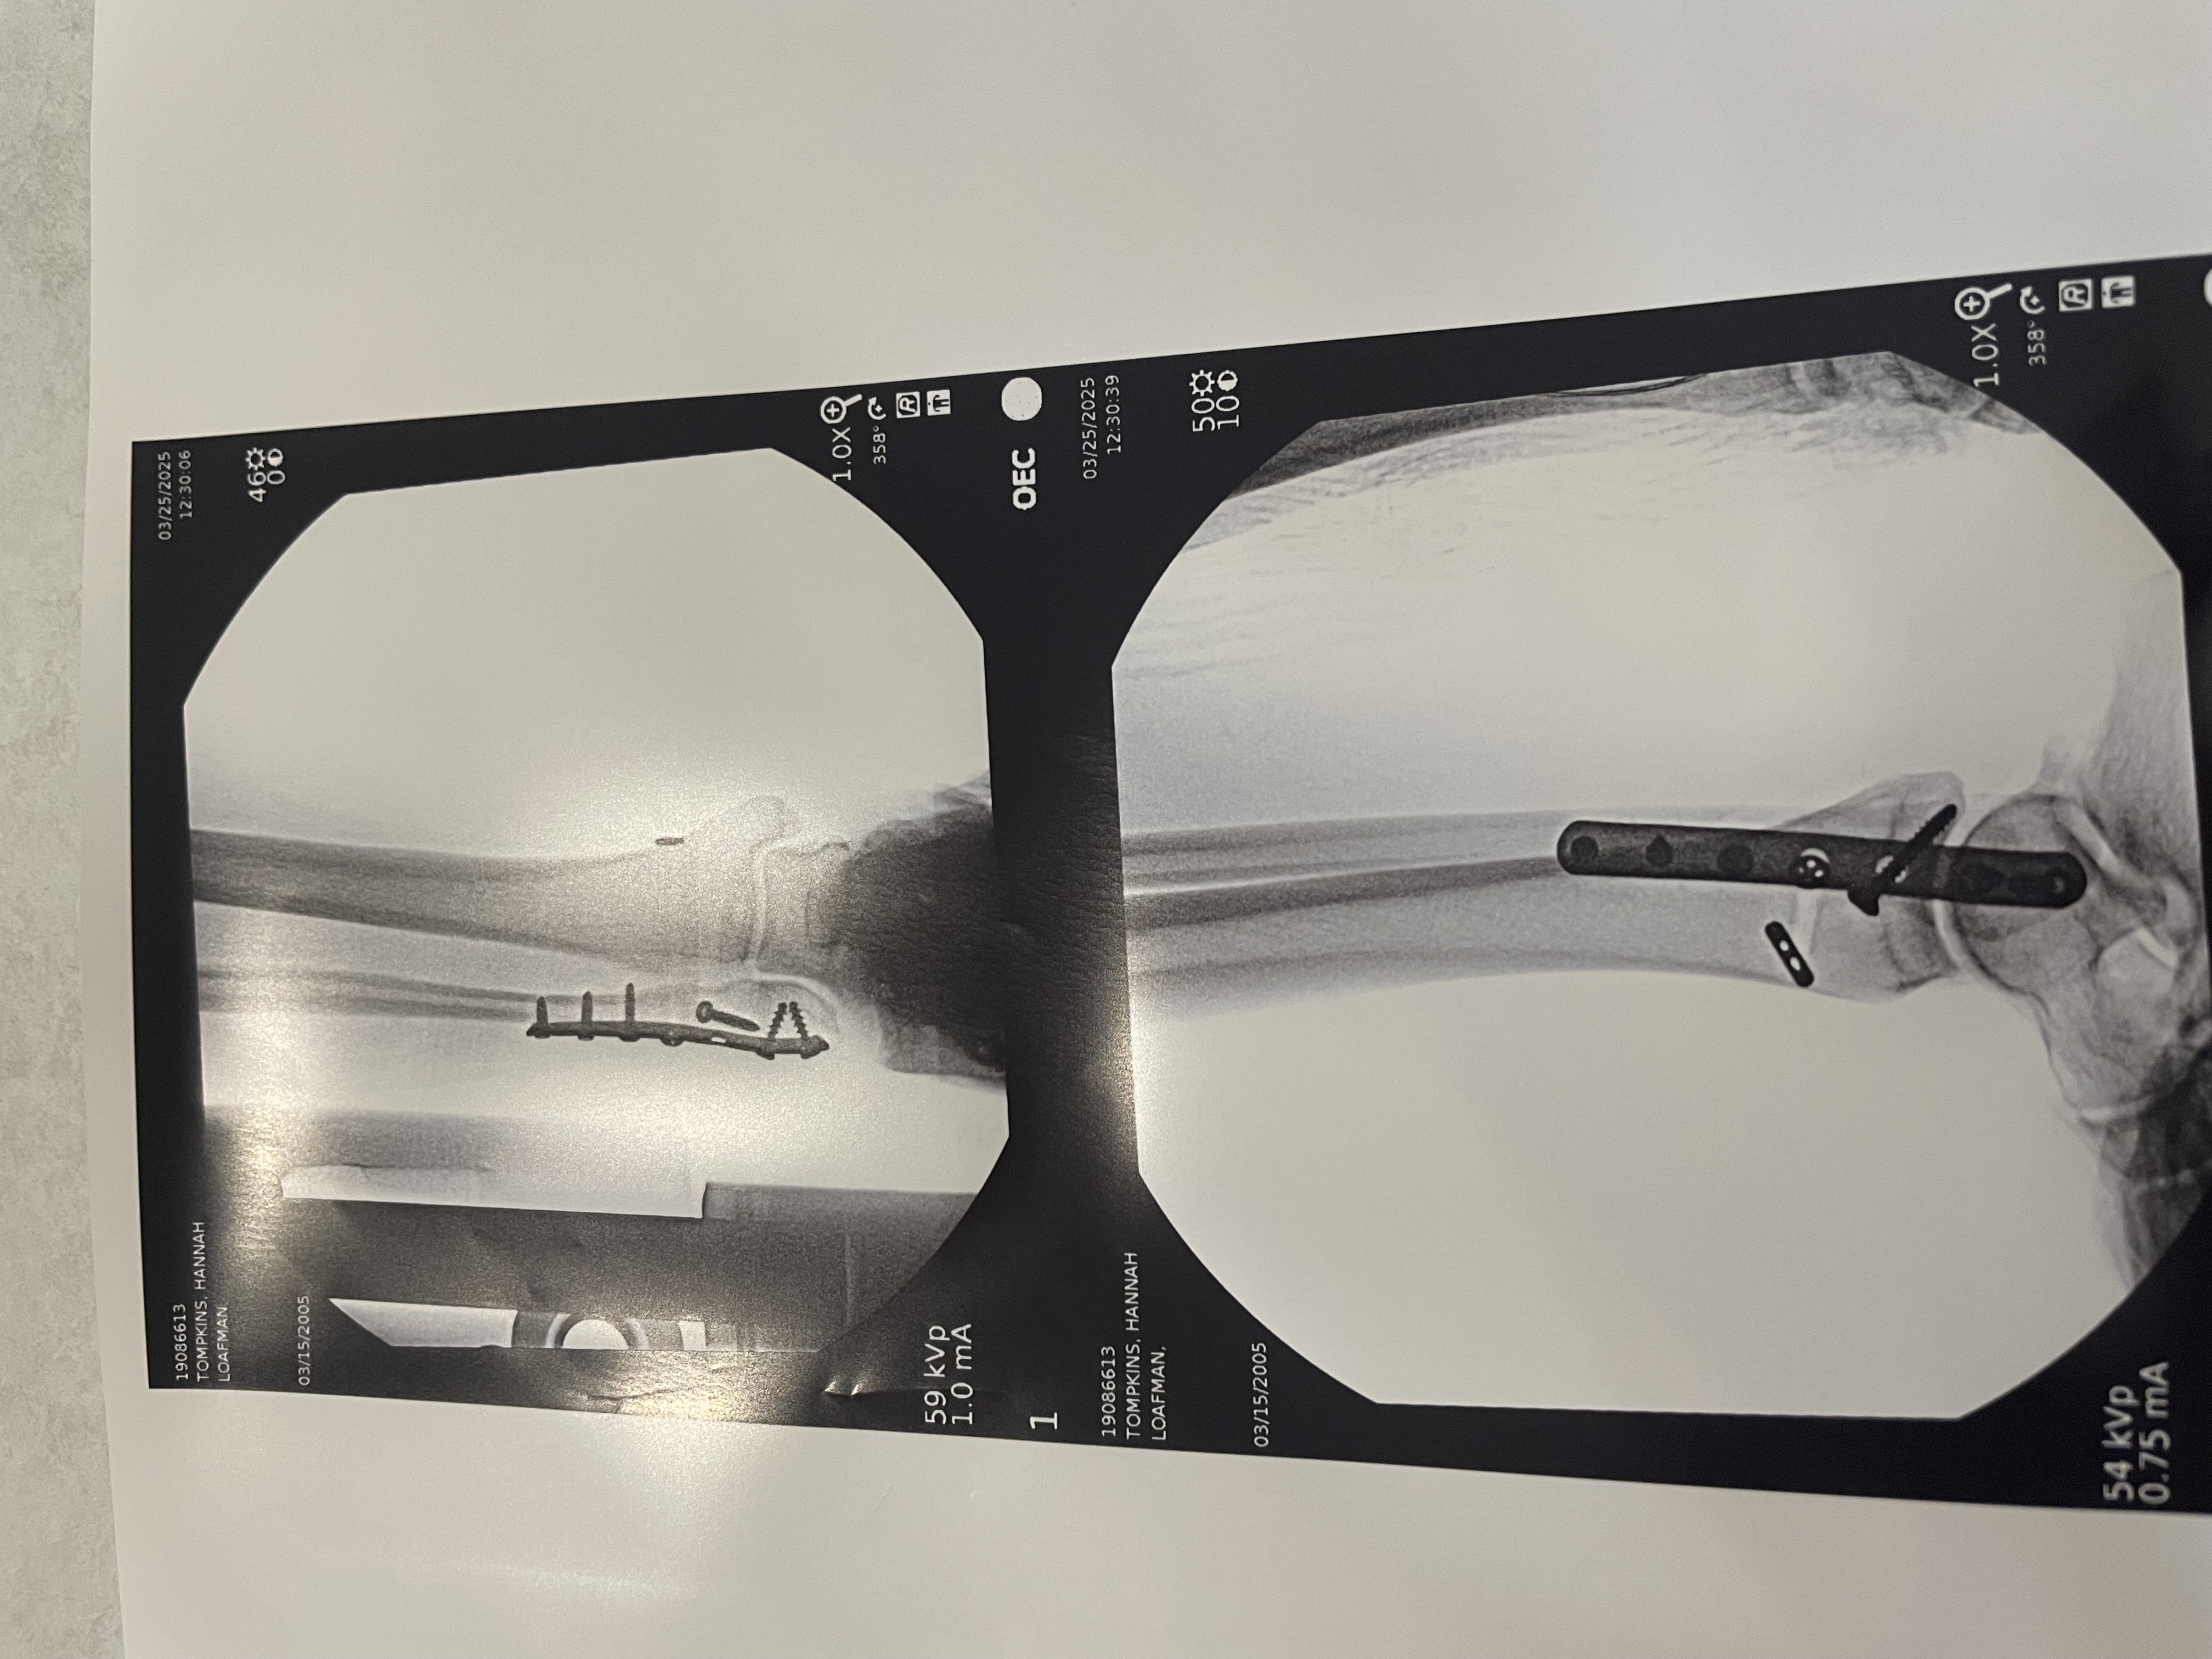

Hi, my name is Hannah Tompkins. On Saturday March 22nd I broke my ankle and on Monday March 25th I had surgery. I am currently non weight bearing, I am out of work for about a month so anything helps! I have bills to pay and groceries I need which is becoming difficult due to not being able to work. Again, anything helps and would be greatly appreciated!